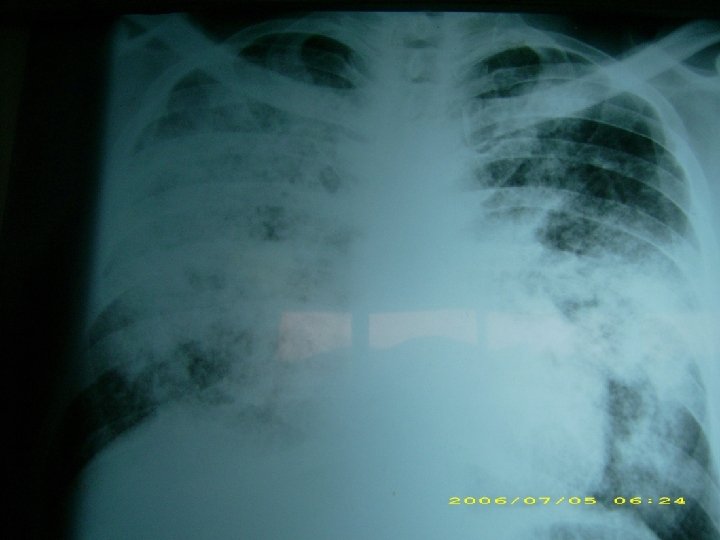

SARS

NEUMONIA AGUDA Caracteristicas clínico-radiológicas Etiología bacteriana: consolidación lobar, cavitación y derrame pleural. Compromiso difuso bilateral: etiología viral, neumonía atípica y por pneumocystis carinii. Staphylococus aureus: de focos múltiples, neumatoceles. Legionella: de focos múltiples, progresión radiológica rápida. Necrotizante, con abscesos o empiema: por gramnegativos, estafilococo, por anaerobios.